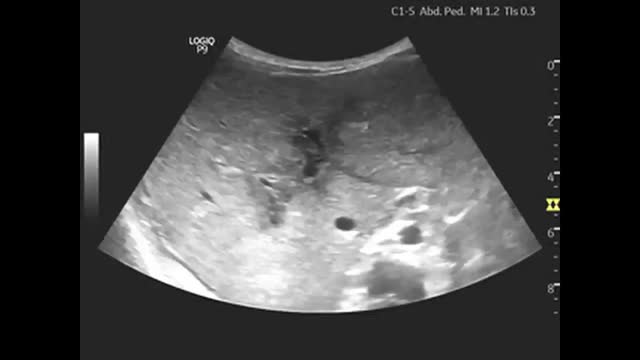

An abdominal ultrasound scan revealed hepatomegaly with periportal hypoechogenicity around the main portal vein and its branches (Figs. 1 and 2), and mild splenomegaly with multiple accessory spleens in the hilum (Fig. 3). The patient was referred to the corresponding referral hospital due to suspicion of myeloproliferative disease, where he received a diagnosis of acute myeloid leukaemia.